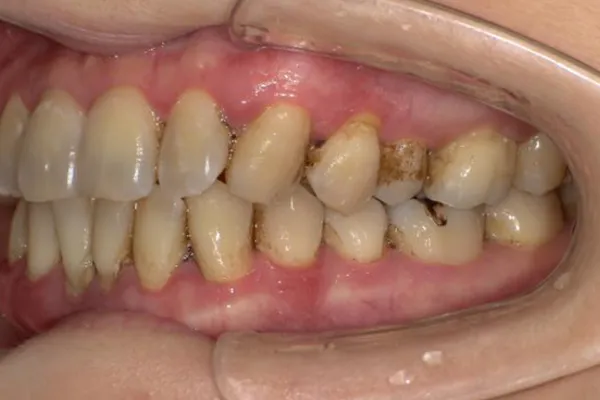

重度歯周病の治療法

歯周病とは、原因の一番は細菌感染により引き起こされるものです。FMD(フルマウスディスインフェクション)とは、一回の治療で歯茎の中の汚れを超音波などの器具を用いて除去し、また同時に抗菌薬を投与して、口腔内の細菌を一度に除去する方法です。そのため治療回数を少なくすることができる点、歯周外科治療を避けたい方にメリットがありあす。保険診療では、歯茎の中のクリーニングは4〜8回に分けて行われることが多いため、クリーニングを行ったところにまた炎症が波及してしまうことがあります。FMDでは、一度にクリーニングすることにより、口腔内の炎症を一気に沈静化することが期待されます。

歯周病により破壊された、歯茎や骨を人工骨や成長因子などを用いて再生させる治療方法です。

将来的に抜歯となるリスクの高い歯などを歯周組織を再生させ、歯を長持ちさせることを目的とします。歯周病でダメになった歯をどうしても残したい方、歯ぐきや歯槽骨を元に戻して歯の寿命をしっかり伸ばしたい方に適応される治療方法です。 -

歯周病治療を行うと歯茎が下がったとよく聞きます。残念ながら、炎症が長期に渡り存在していた歯茎や、重度歯周病では、治療を行うことにより歯茎が下がり炎症が除去されると歯茎が下がってしましやすいです。そういった場合、セラミックス治療を行うことで審美的に改善を図ることがあります。

また、歯周病はないのに、歯茎が下がってしまうことによる審美性が損なわれてしまう病気があります。そのような場合、歯茎の移植などを行うことにより、歯を削ることなく審美性を改善させることができます。 -